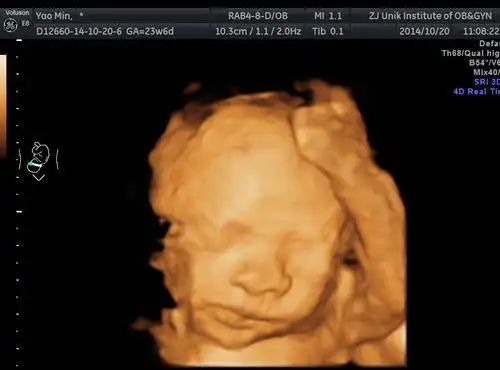

孕妇做四维彩超胎儿鼻子扁又大胎儿也是有苦说不出啊